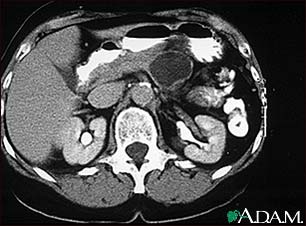

Pancreatic, cystic adenoma - CT scan

A CT scan of the upper abdomen showing a large cyst in the pancreas (cystic adenoma of the pancreas) seen on the upper right side of the picture.